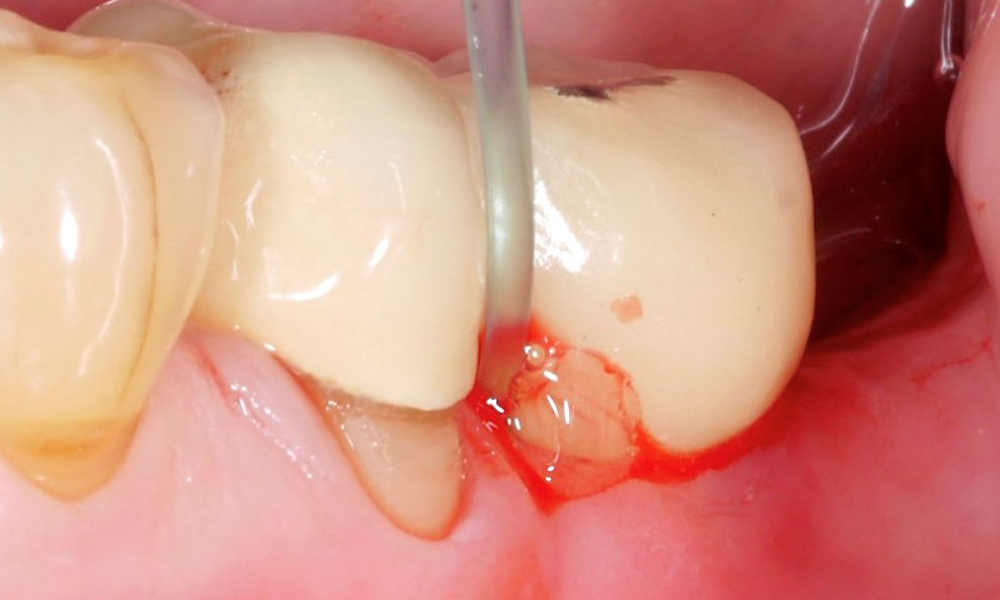

Ефикасното и успешно почистване на повърхността на импланта със сигурност е един от най-важните фактори при лечението на случаи на периимплантит. В предишен доклад („Нехирургично лечение на периимплантит – златен стандарт ...?“), резултат от 18-ия Европейски семинар по пародонтология, който се проведе през есента на 2022 г., беше обсъдена темата за механичното почистване при лечение на периимплантит. Съществува обаче и възможност за подпомагане на това механично почистване на повърхността на импланта с допълнително химическо почистване.

Съществуващите доказателства за допълнително химическо почистване на повърхността на импланта бяха обобщени от de Waal и колеги (2022). За съжаление тук – подобно на механичното почистване – стигаме до заключението, че все още има твърде малко добре проведени проучвания, за да се предоставят ясни насоки при лечение на периимплантни състояния. Тази изследователска група успя само да идентифицира и обобщи три проучвания на тема „химическо почистване“ и ги резюмира в систематичния преглед.

Две проучвания изследват ефекта на антимикробната фотодинамична терапия, а другото проучване ефекта на гел, специално за почистване на повърхността на импланта. И в трите проучвания тези химични методи са използвани в допълнение към субмукозно механично почистване, което се състои например от ултразвуково и/или въздушно полиране. И трите проучвания показват по-добри резултати по отношение на намаляването на дълбочината на сондирания джоб, докато всички други параметри, като кървене при сондиране или успех на лечението, са неубедителни.